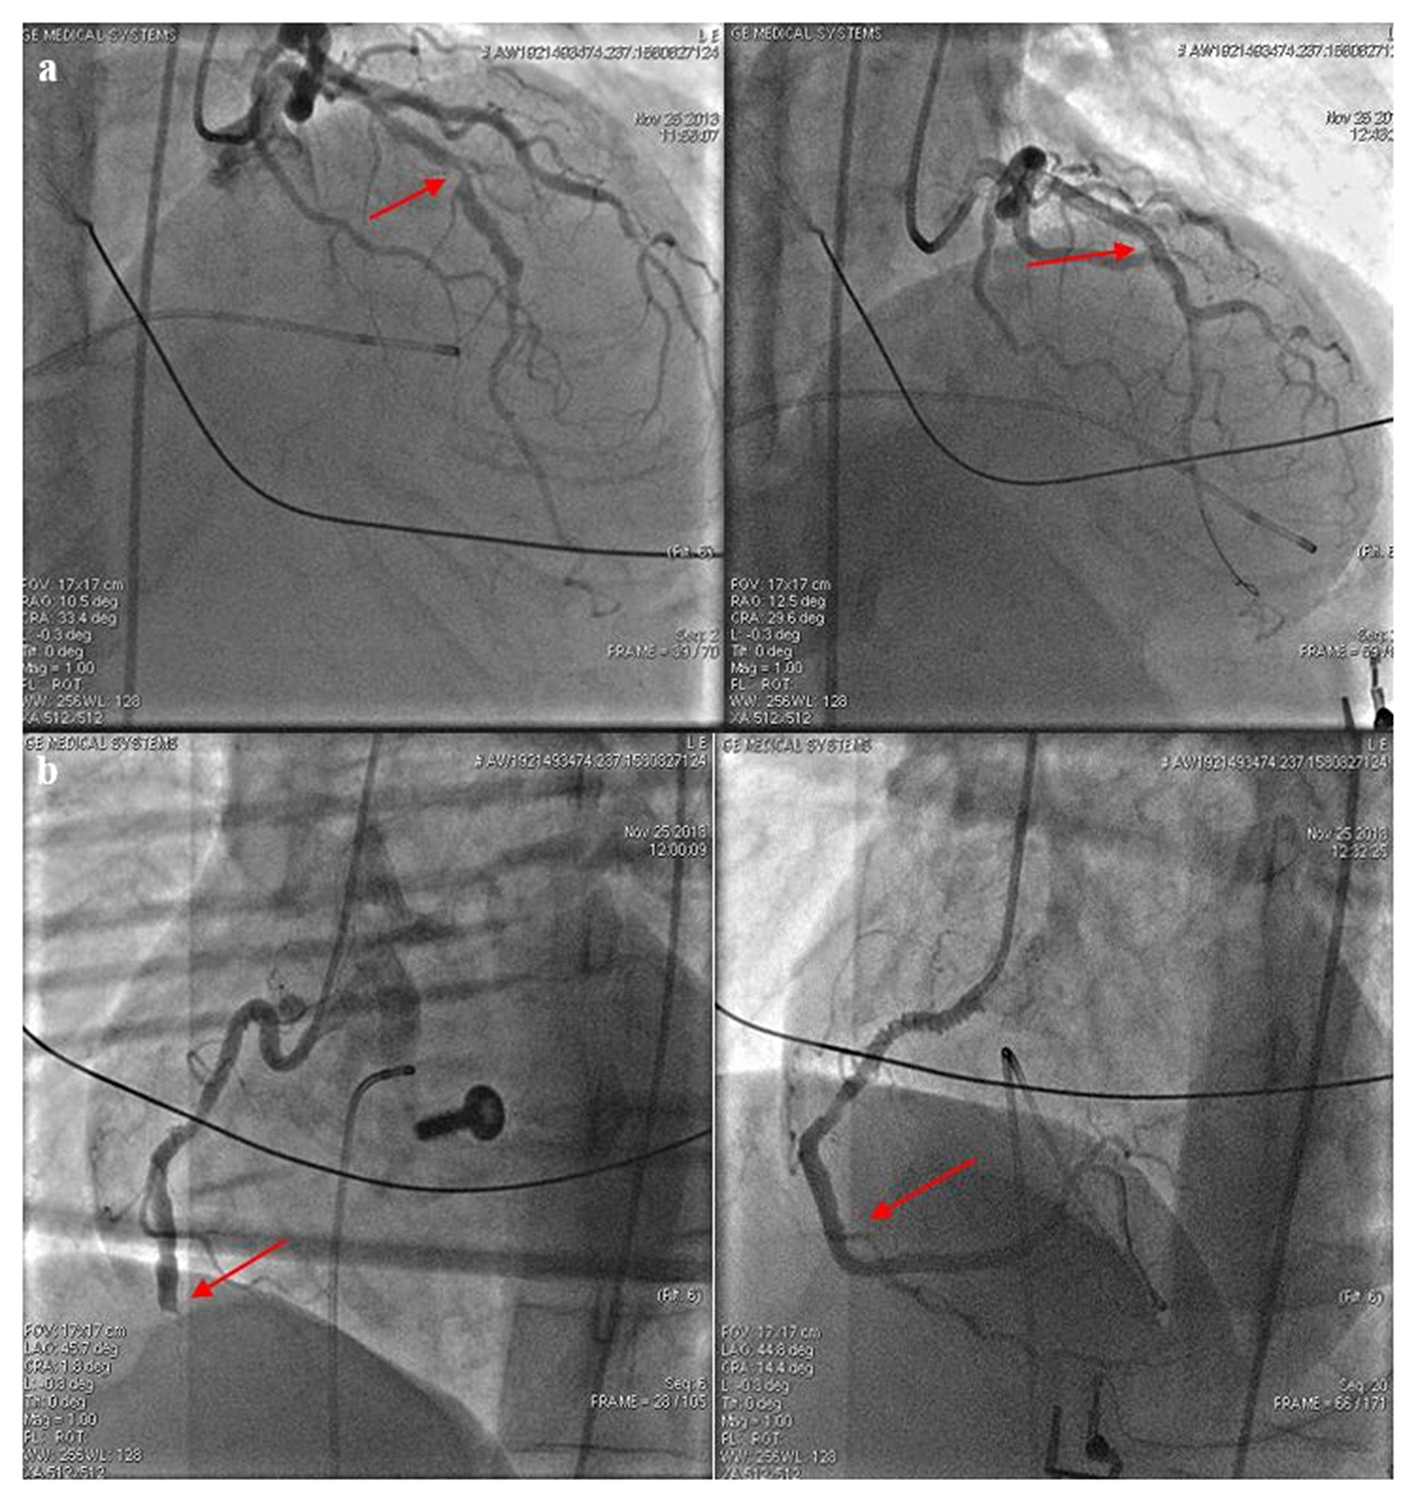

On the day of the call, at 8:45, she complained of chest pain and numbness in her left arm and then at 9:48, suddenly she lost her consciousness. The relatives called the emergency at 9:50 and the ambulance unit arrived at the scene 5 min later. Bystander CPR was not attempted; her family members did not even check her vital signs. During the primary assessment, the patient showed no signs of life, her pupils were dilated and non-reactive to light. At 9:56 the ambulance crew immediately started performing manual chest compressions. The initial rhythm proved to be ventricular fibrillation (VF); therefore, at 9:58 they performed defibrillation using an energy level of 200 J and continued the resuscitation by strictly adhering to the Advanced Life Support (ALS) cardiac arrest algorithm. LUCAS-2 mechanical chest compression device was applied and used in a continuous mode. Despite a total of five shocks (200–360–360 J), the VF still persisted. However, following the fifth shock, her rhythm changed to P-wave asystole. A total of 8 mg of epinephrine and 450 mg (300 + 150 mg) of amiodarone were given during the CPR. Considering the patient's initial complaints, acute coronary syndrome was suspected as the underlying condition. When the ambulance left the scene, mechanical chest compressions had already been carried out for 50 min. During the transport to the hospital, she received 500 ml of crystalloid solution and 2 g of magnesium sulfate; furthermore, 250 mg of dobutamine (3.6 μg/kg/h) and 100 mg of dopamine (8.2 μg/kg/h) were administered in a continuous infusion due to persistent arterial hypotension [target mean arterial pressure (MAP) 50 mmHg]. Arriving at the hemodynamic laboratory an intracavital pacemaker electrode was led to the right ventricle through the right femoral vein due to complete atrioventricular block. After that, she still had no spontaneous circulation, thus coronary angiography was performed with ongoing mechanical chest compressions. It revealed an 80% stenosis in the middle segment of the left anterior descending artery (LAD) and a distal occlusion of the dominant right coronary artery. Coronary angioplasty was carried out on both arteries with stent implantations (Figures 1a,b).

Figure 1

(a) The left anterior descending artery (LAD) before and after stent implantation. After predilation at 14 atm, a 3.5 × 30 mm Integrity stent was positioned into the stenosis of the LAD. Red arrows indicate the sites of intervention. Images taken before (left picture) and after (right picture) the intervention. (b) The right coronary artery (RCA) before and after stent implantation. During the intervention, a dissection developed at the extremely tortuous ostium of the RCA; to this site a 3.5 × 24 mm Omega stent was placed after predilation at 15 atm (marked with right arrow). A 3.5 × 12 mm Omega stent was implanted to the distal area resulting in a Thrombolysis In Myocardial Infarction (TIMI) grade 3 flow.